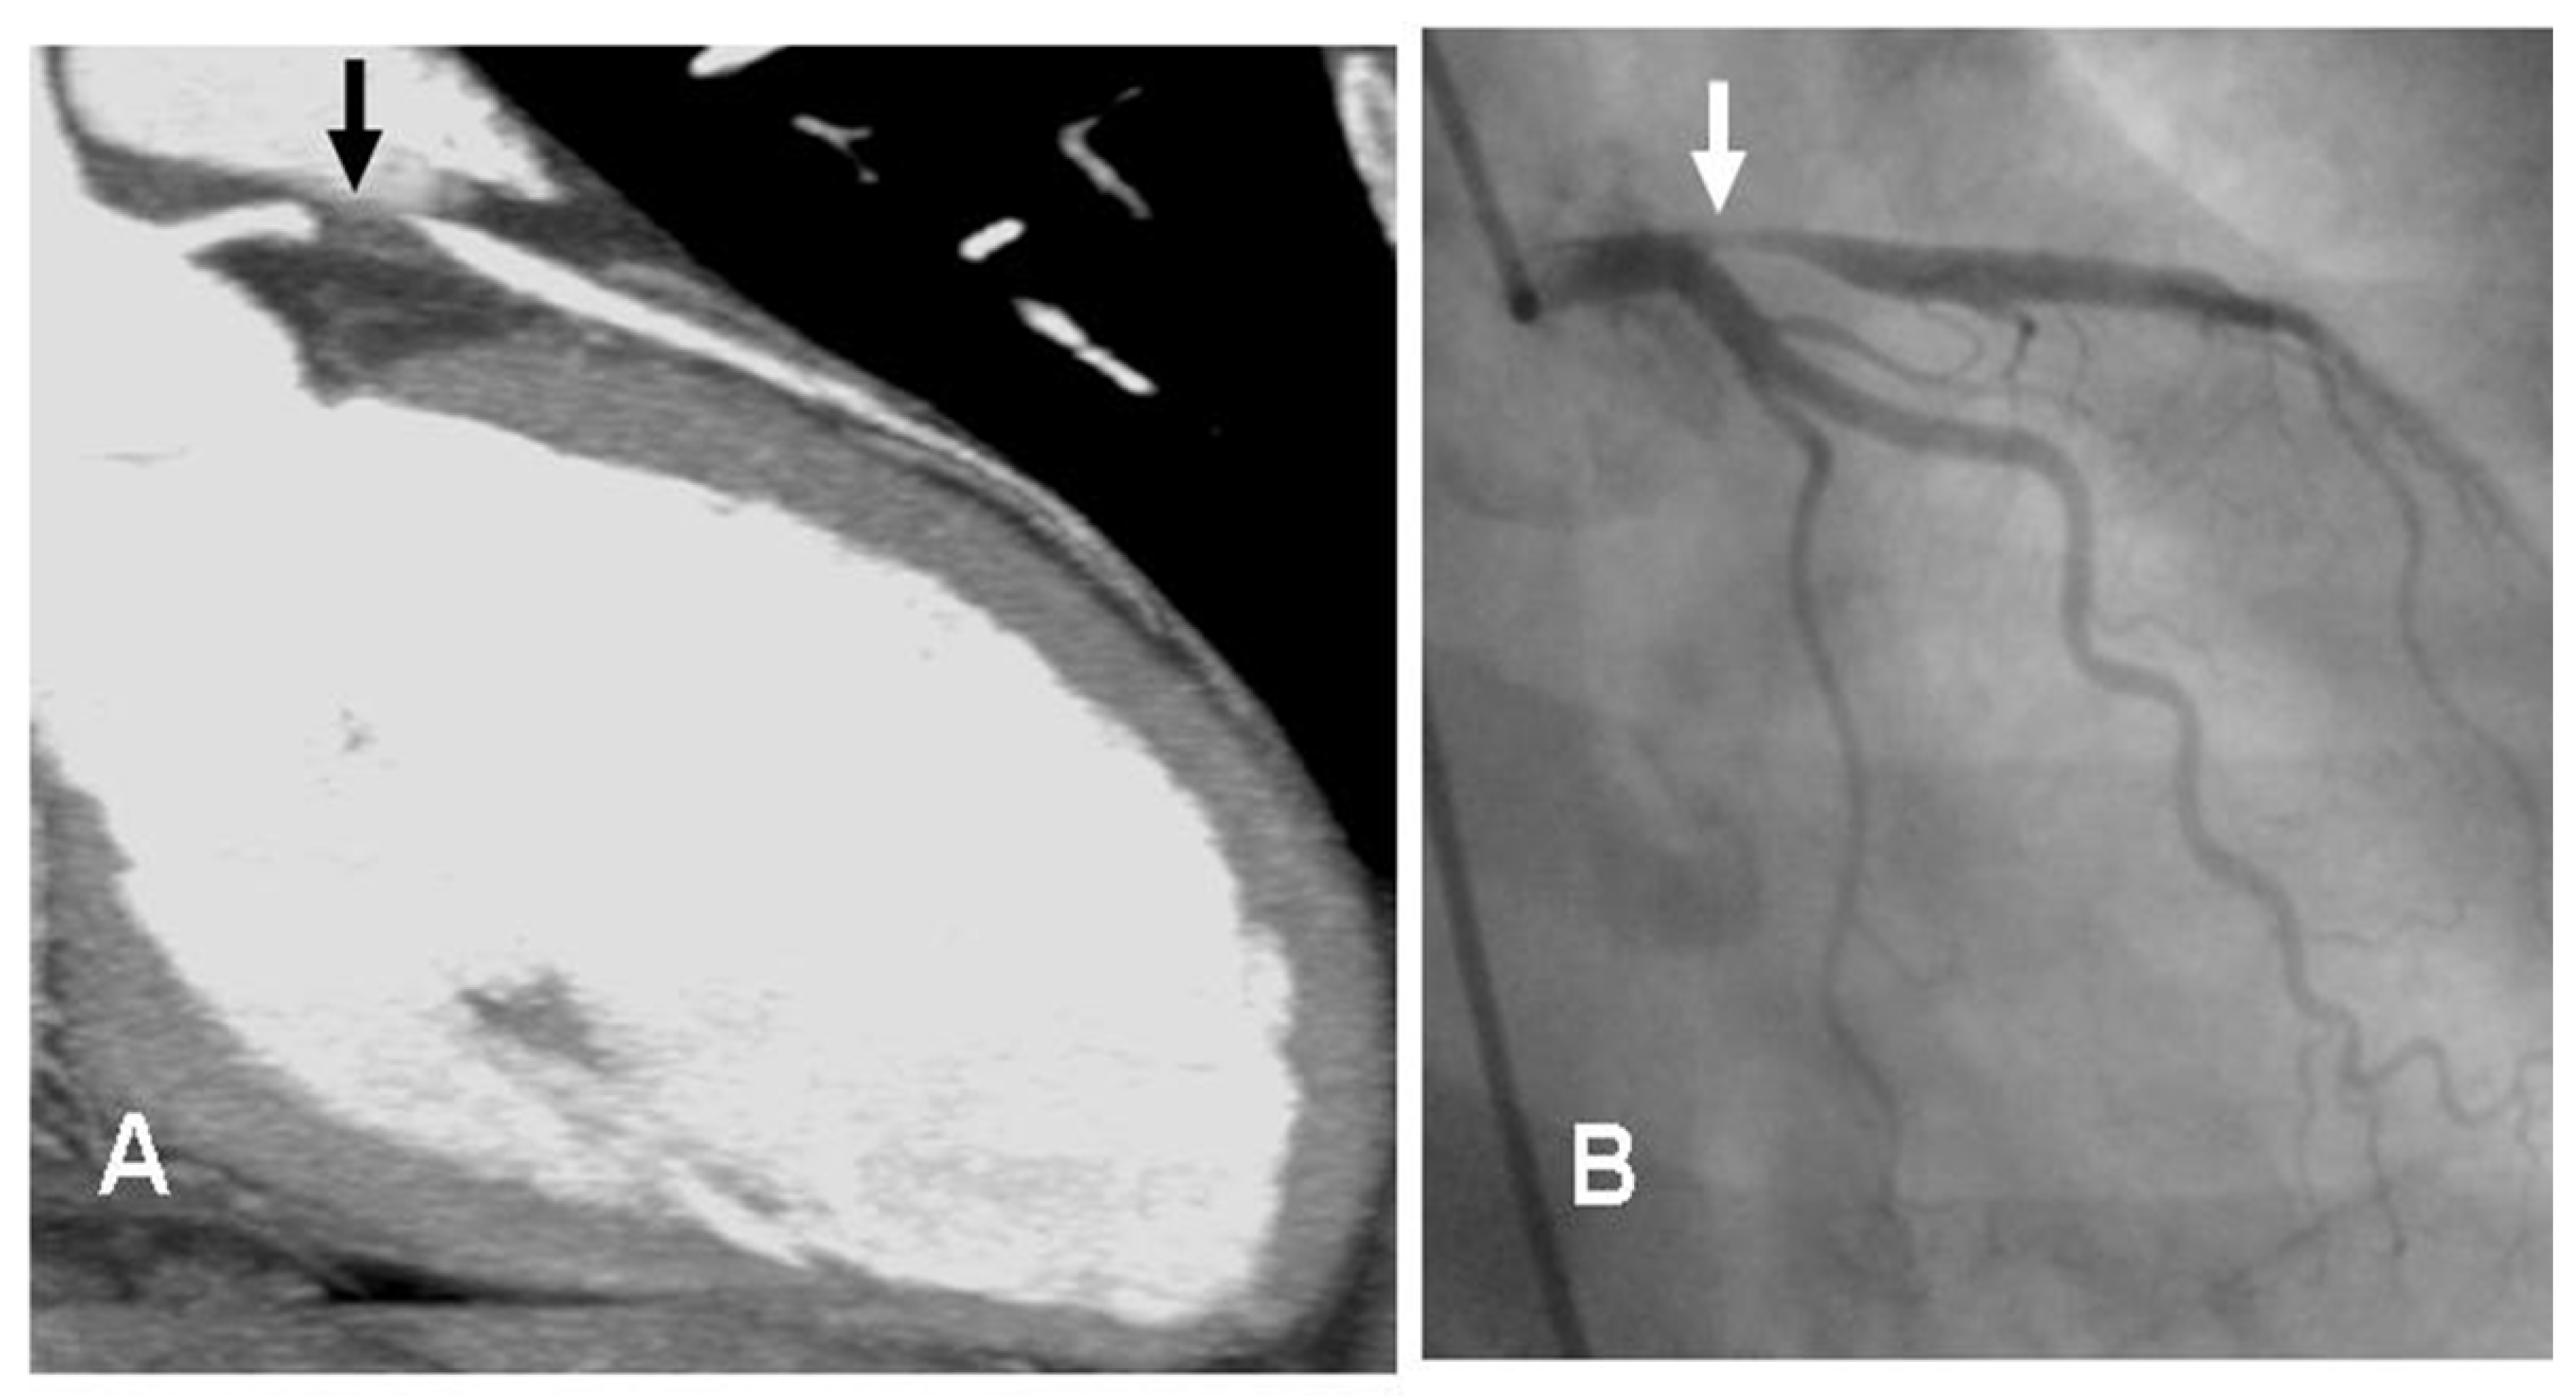

- Although the role of nuclear imaging in TTS has not yet been well established in clinical practice, assessments of myocardial perfusion, adrenergic innervation and metabolic activity may help in the diagnosis [88,89]. For instance, if there is normalized LV wall motion, the delayed recovery of glucose metabolism (by FDG-PET) and sympathetic innervation (by 123I-MIBG scintigraphy) may allow for the diagnosis of TTS in patients with delayed presentation. Although the coronary microcirculation is transiently compromised in TTS, its physiological role is still unclear. A reduction of perfusion tracer counts as a result of regional myocardial wall thinning at the apex, due to both artefacts and partial volume effects, which may mimic ACS, has been reported [86]. Figure 4 (SPECT-MPI) and Figure 5 (CMR) present the case of a patient with TTS.